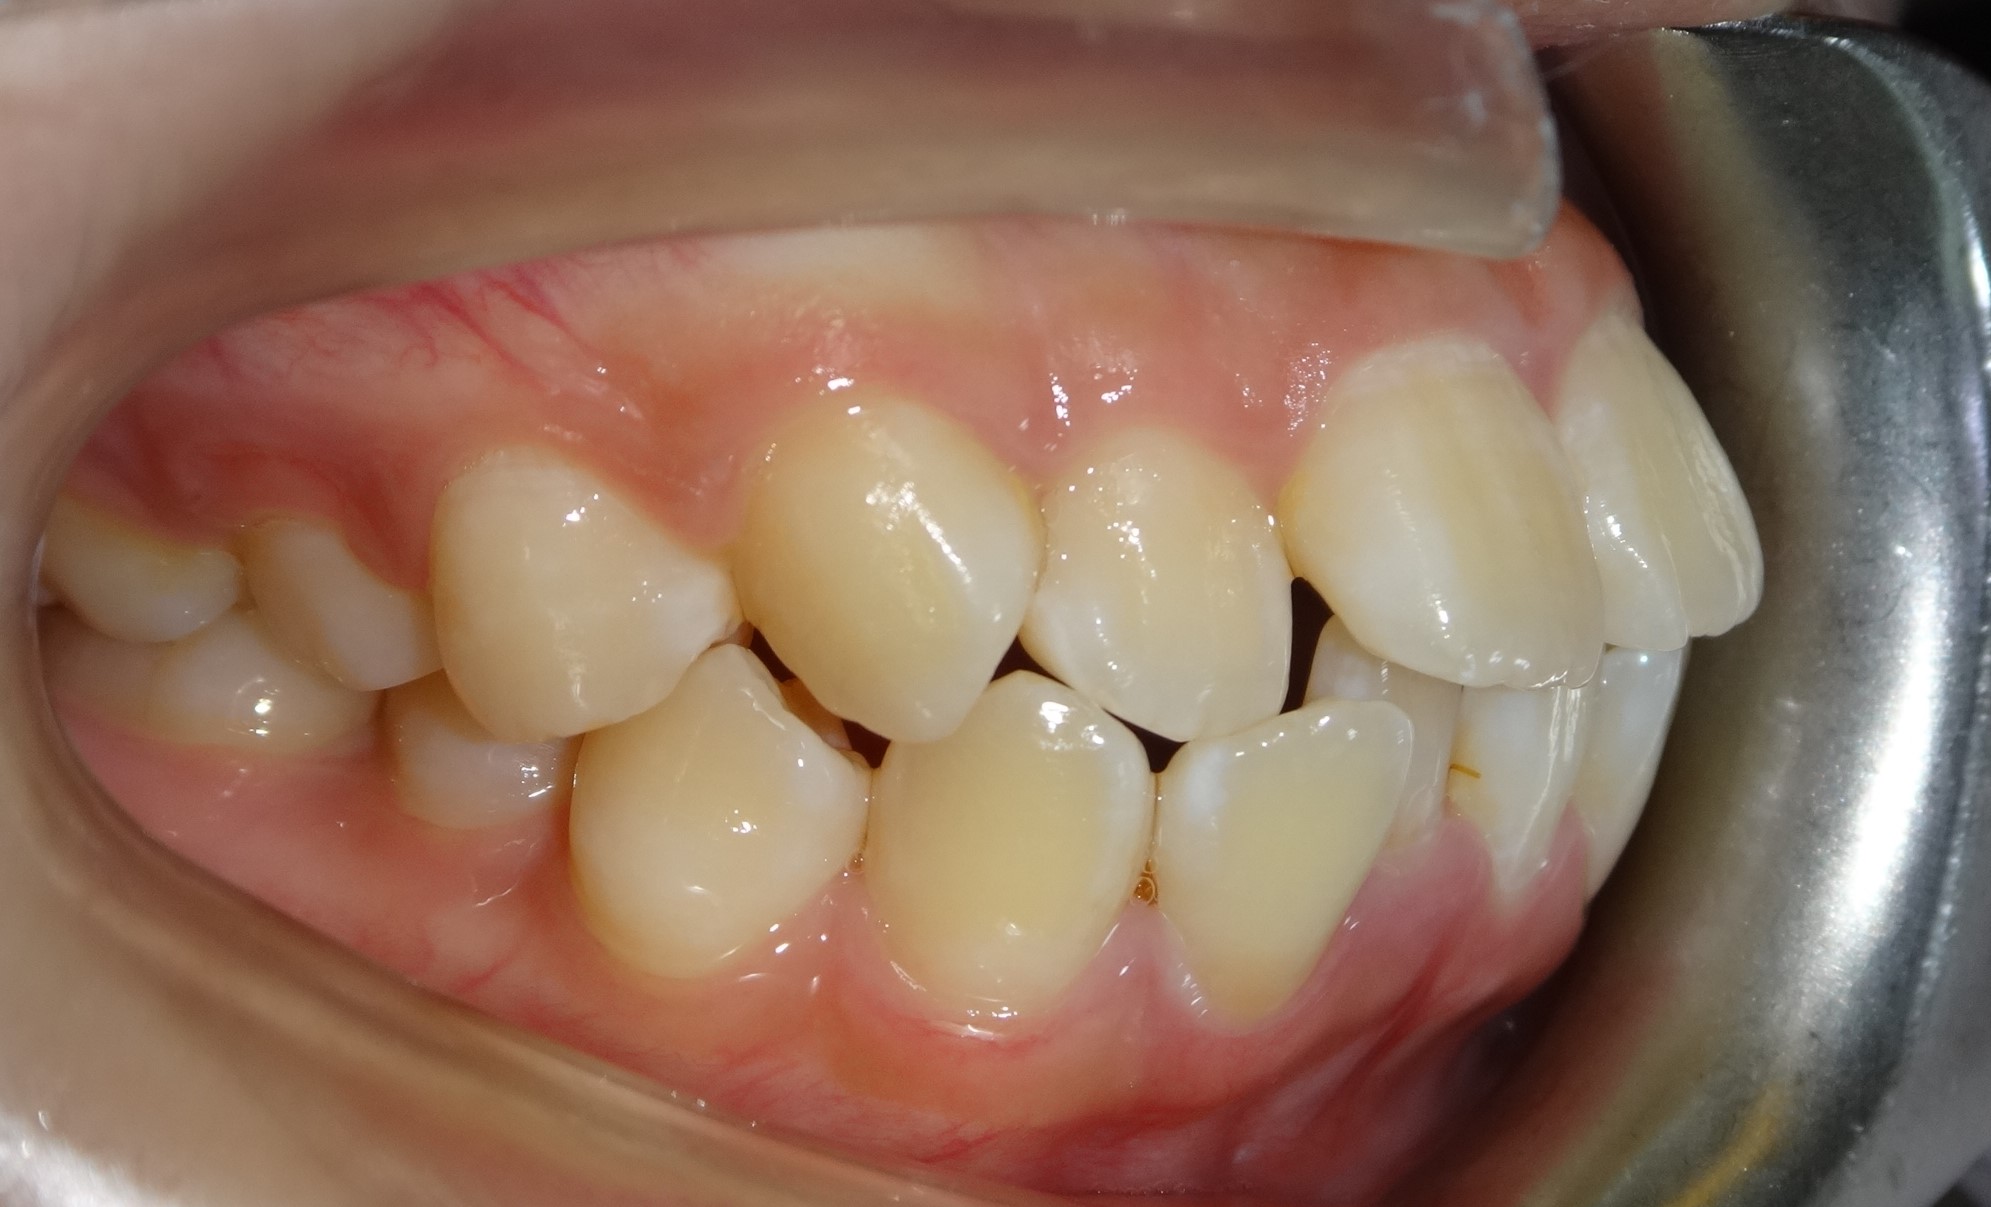

拔牙案例 首頁 案例分享 齒顎矯正 拔牙案例 - 拔牙案例 - 年紀:15歲 矯正方式:隱適美隱形矯正 時間:30個月 主訴:暴牙、笑起來不好看、咬合不正 矯正前 矯正後 矯正前 矯正後 矯正前 矯正後 聲明:本所療程皆由專業醫生評估後,依照個人口腔狀況進行治療。因每位患者個別狀況不同,術後狀況也不盡相同,需親來本所由醫生評估。